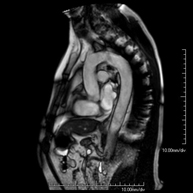

Prueba diagnóstica no invasiva que consiste en la obtención de imágenes de alta definición anatómica de la pelvis mediante el empleo de un campo electromagnético y ondas de radio (con un emisor y un receptor). No utiliza radiación ionizante. Se realiza para estudiar patologías del útero, del ovario, de las trompas y la vagina, ya sean de origen tumoral, inflamatorio o vasculares. Además permite valorar les estructuras adyacentes localizadas en la pelvis, identificando sus alteraciones. A veces requiere el uso de contraste intravenoso (Gadolinio) para caracterizar las lesiones. - RM Pelvis masculina